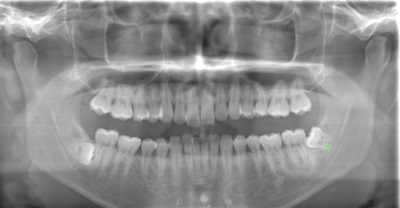

CASE 8

| 年齢・性別 | 39歳・男性 |

| 主訴 | 左上下 親知らず抜きたい |

| 抜歯期間 | 30分 |

| 抜歯費用 | 約2,500円(保険内) 別途CT撮影で3,000円 (2022年7月現在) |

| 抜歯内容 | 左上下の親知らず抜歯 |

CASE 9

| 年齢・性別 | 27歳・女性 |

| 主訴 | 左上親知らず抜きたい |

| 抜歯期間 | 10分 |

| 抜歯内容 | 左上の親知らず抜歯 |

CASE 10

| 主訴 | 左上下親知らず抜きたい |

| 治療方針 |

親知らずは抜いたほうが良い認識はあったものの、痛みや腫れが出ることを知って、勇気が出ないままでいたとのことでした。 そのまま放置していたら虫歯になってしまい、今回ご来院されました。しっかりと麻酔をして緊張をほぐしながら抜歯を始めました。完全萌出のため、時間を要することなくすぐに抜歯することができました。 |